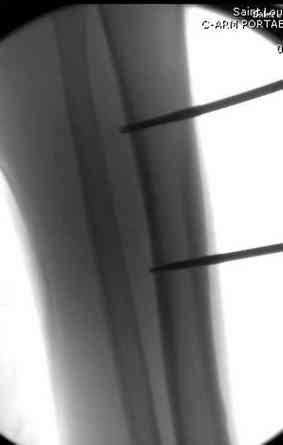

Огнестрельный дефект костей и передней группы мышц, поступил с юнилатеральным аппаратом, стабильность плохая, из раны обильное гнойное

отделяемое. #1;#2. Стержневой апп. снят, наложен апп. Илизарова, дренажно-ирригационная система промывки раны. #3; #4. После стихания инфекции,

аппаратом постепенно создана рекурвация для сближения контактов мышц (сухожилий) передней группы голени. #5;#6. Наложен шов на сухожлилия М.

Tibialis anterior и M extensor digitorum L. Одновременно компактотомия костей голени в В/3 для замешение дефекта костей. #7;#8. Постепенно

исправлена ось и возмещен дефект. В результате восстановление тыльной флекcии стопы и функции конечности. #9;#10;#11